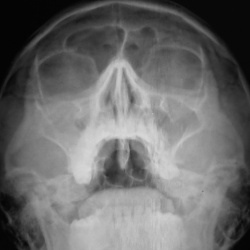

Отоларингологом направлен на рентгенографию ППН